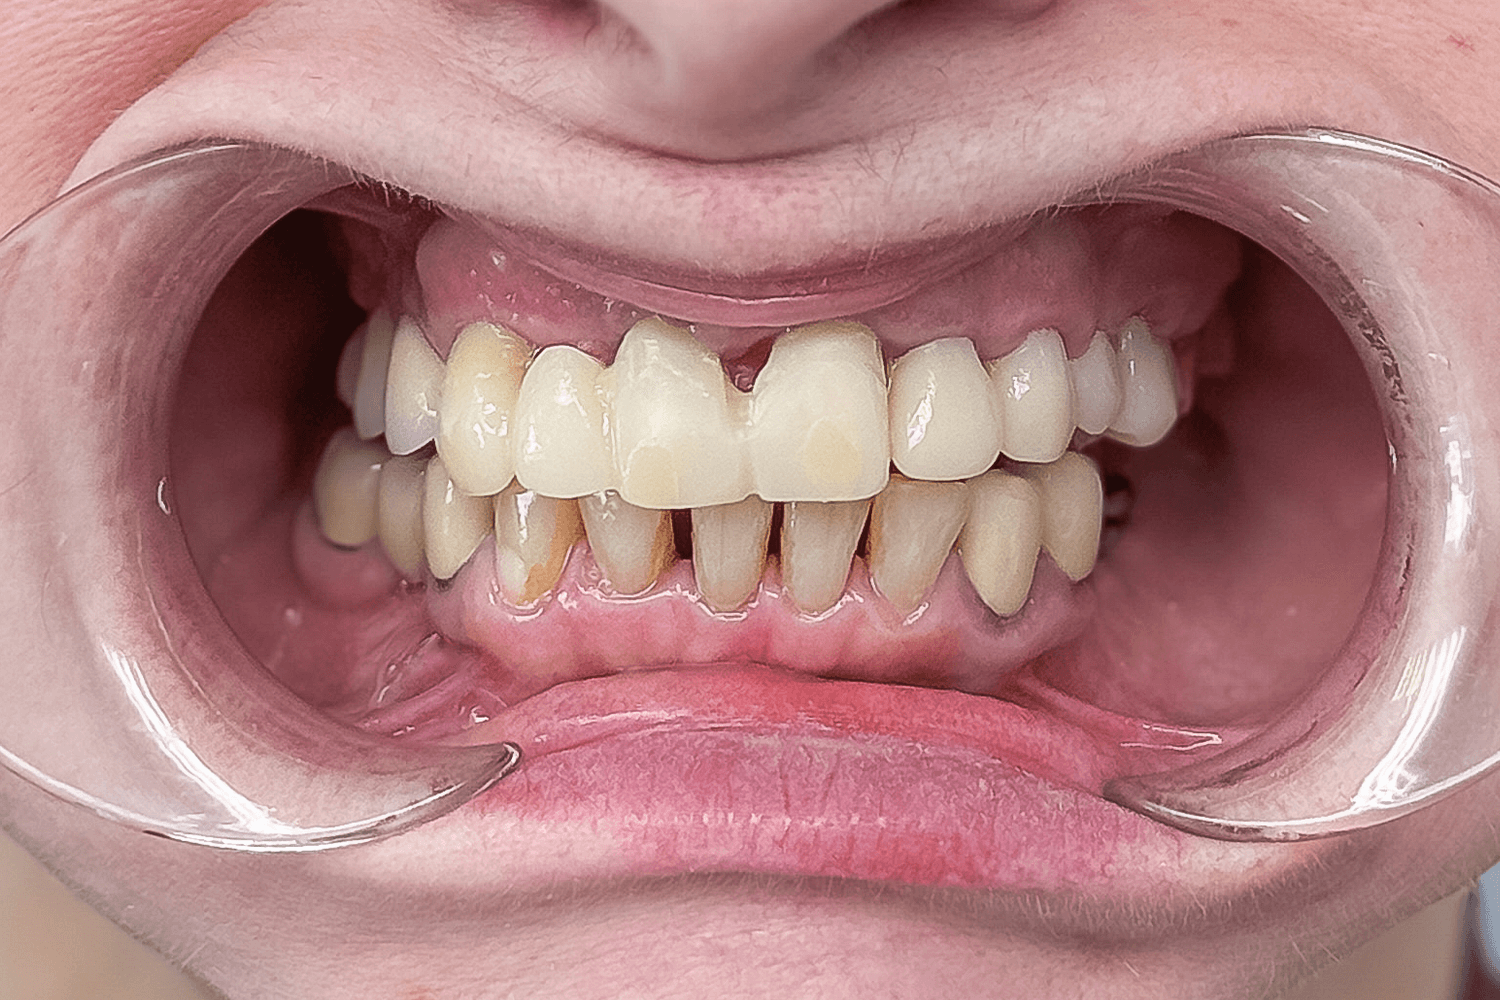

В нашу клинику обратилась пациентка со следующими жалобами: эстетический дефект фронтального участка верхних зубов, сложности при пережевывании пищи и ненадежная фиксация мостовидного протеза на верхней челюсти. По словам пациентки, около 5 лет назад ей провели протезирование передних зубов верхней челюсти, но эта конструкция регулярно расцементировалась.

После анализа данных полученных путем компьютерной томографии и при очном осмотре было обнаружено:

- Установленный мостовидный протез на зубах 4.4 и 4.6 (зуб 4.5 отсутствует).

- Зубные коронки на зубах 3.3 и 3.4

- Зубы 3.6 и 3.7 отсутствуют.

- Имплантаты в области недостающих зубов 1.4, 1.6 и металлокерамический мостовидный протез на них с винтовой фиксацией.

- На зубах 1.3, 1.2, 2.1, 2.2, 2.3, 2.6 и 2.7 (2.4 и 2.5 отсутствуют) установлен металлокерамический мостовидный протез на родных зубах, который был подвижен и снимался вместе с вкладками.

- Зубы 1.2, 1.3 и 2.1 расколоты.

- Зуб 1.5 отсутствует.

- Кариозное поражение зуба 2.8

- Зубы 1.6 и 1.7 депульпированы.

- Катаральный гингивит на слизистой верхней челюсти (как следствие регулярного раздражения от подвижного металлокерамического протеза).